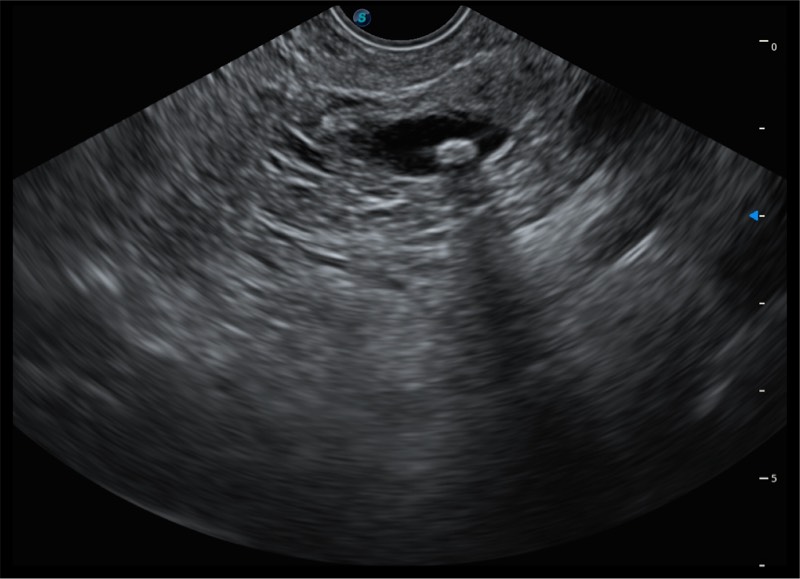

基于二十年的超声技术积累,银河集团官网提供了最新一代的独立超声主机,在提供高质量图像的同时满足多学科使用。具备常见多普勒技术并提供弹性成像、声学造影等高端影像技术。新一代传感器具有更强的抗干扰能力并减少图像伪影。

4-12MHZ宽频输出